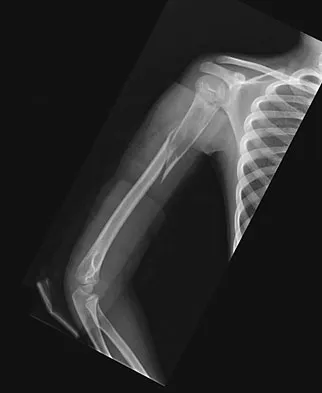

An 11-year-old boy has right shoulder pain and has been unwilling to use the arm after throwing a baseball in a Little League game 3 weeks ago. Examination reveals upper arm and shoulder tenderness with swelling. A radiograph and MRI scan are shown in Figures 27a and 27b. Management should consist of

Explanation

The radiograph is consistent with a unicameral (simple) bone cyst. The MRI scan reveals that the cyst is juxtaposed to the physis and therefore can be classified as active (latent cysts are more than 1 cm away from the physis). Active cysts are treated with aspiration and steroid injection, although repeated injections may be necessary. Curettage and bone grafting results in more reliable healing but may lead to growth arrest in active cysts. Iannotti JP, Williams GR: Disorders of the Shoulder: Diagnosis and Management, ed 1. Philadelphia, PA, Lippincott Williams & Wilkins, 1999, pp 945-946.